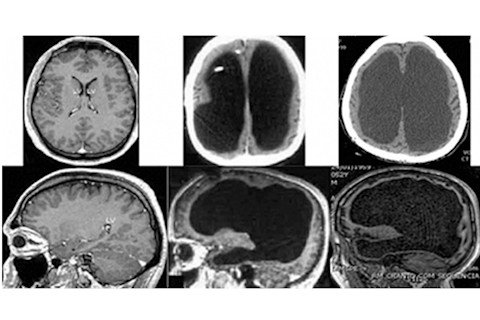

Here’s Forsdyke’s illustration: a normal adult brain on the left, alongside two striking adult post-hydrocephalic ones. The black spaces are nothing but fluid:

Brain scans. Normal adult appearance (left). Enlarged ventricles (middle and right). (Credit: Forsdyke 2015 Biological Theory; Reproduced under Creative Commons License from Forsdyke 2014 Frontiers in Human Neuroscience)

While the enormous “holes” in these brains seem dramatic, the bulk of the grey matter of the cerebral cortex, around the outside of the brain, appears to be intact and in the correct place – this is visible as the dark grey ‘shell’ beneath the skull. What appears to be missing is the white matter, the nerve tracts that connect the various parts of the cerebral cortex with each other, and with the other areas of the brain.

However, some white matter is still visible as the pale grey layer that borders the holes. The big question is whether this layer of white matter is sufficient to connect up the grey matter and allow it to function normally. There doesn’t seem to be much of it, but on the other hand, we really don’t know how much white matter is strictly necessary.